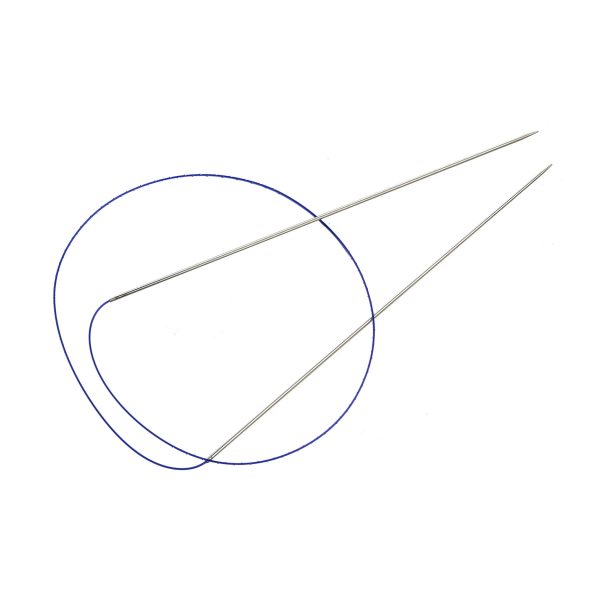

Velvet Dual Lift thread features a unique double needle for achieving a natural and immediate lifting effect in the desired area.

The thread is injected through a single injection site, which significantly reduces the damage to soft tissue.